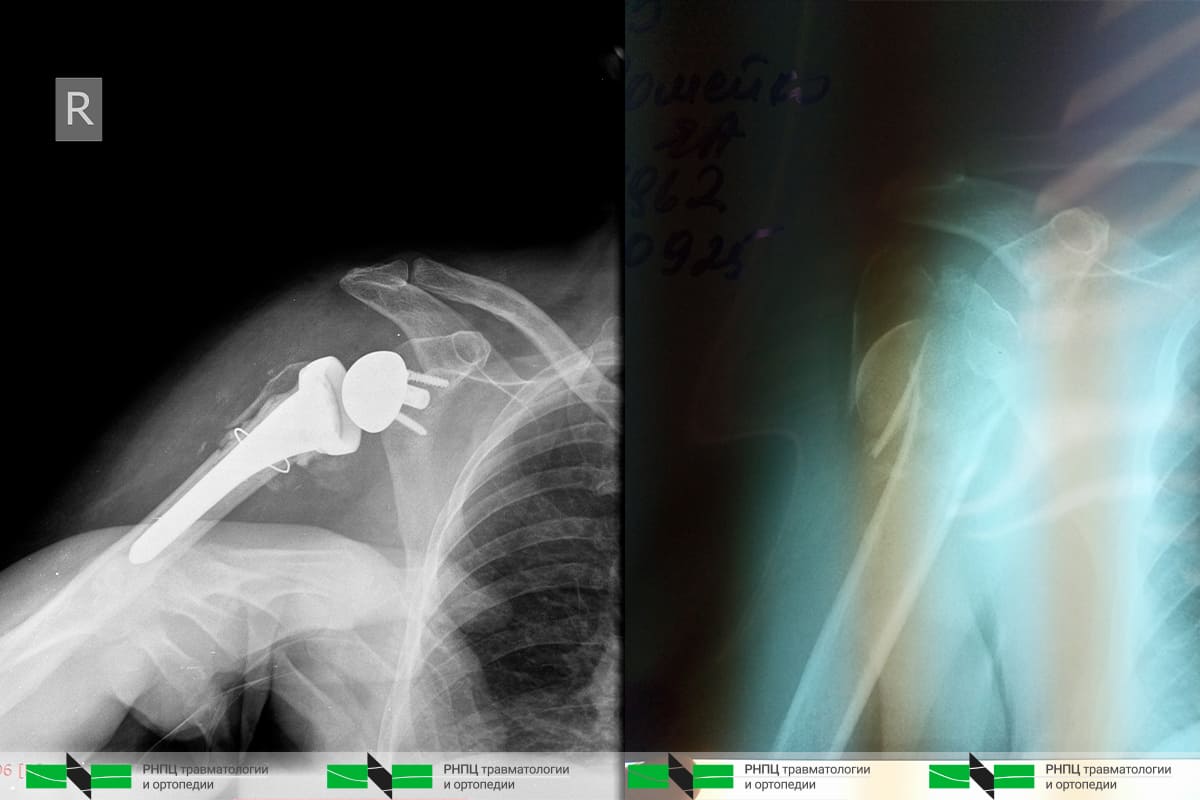

В процессе проведения мастер-класса было успешно выполнено хирургическое вмешательство: реверсивное эндопротезирование плечевого сустава пациентке с закрытым оскольчатым переломом проксимального отдела плечевой кости. Из-за особенностей перелома и смещения фрагментов остеосинтез в таких ситуациях является бесперспективным.